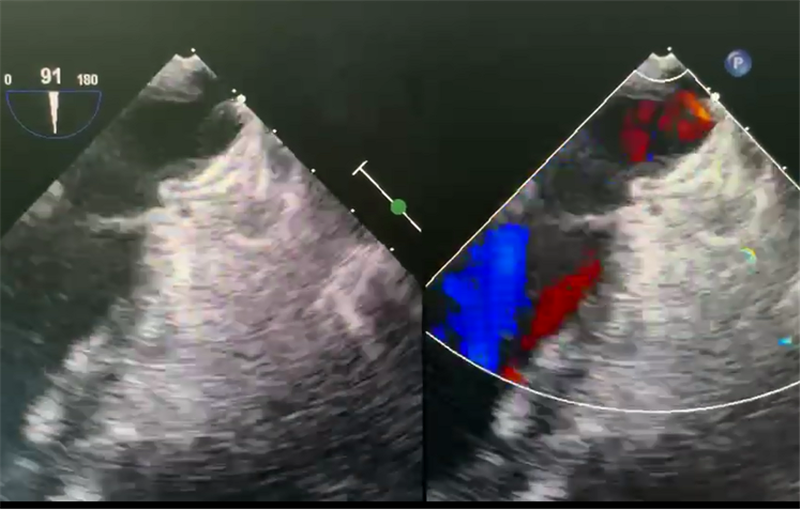

术前,根据CT3D建模显示病人的左心耳为反鸡翅型且心耳开口浅,手术难度高,操作难度较常规要大很多。经过食道超声显示左心耳无血栓,并精准测量左心耳口部与颈部直径。经过陈建军教授及团队严密细致的讨论研究,手术团队制定了安全有效的封堵方案。

术中,陈建军教授团队在介入科、胸心血管外科及超声科的配合下,实时经食道超声引导下进行手术。按照术前制定的方案,综合评估选择了LAmberTM左心耳封堵器进行手术。术中准确地将封堵器导引系统送到病人左心耳内部,一步到位释放封堵器,经食道超声及DSA造影下证实封堵成功,顺利完成了这例复杂经皮左心耳封堵术。

术后食道超声证实封堵良好